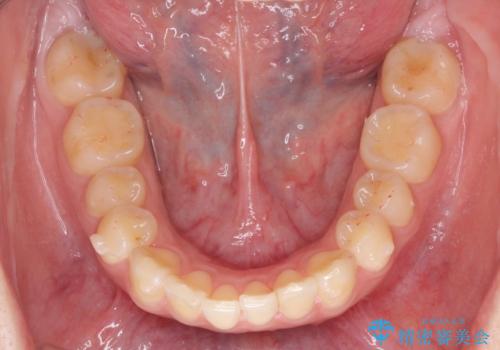

マウスピース矯正で行う出っ歯の治療

- 飛び出したように見える前歯の改善を求めて来院されました。

元々、セラミッククラウンですぐに歯並びを改善したいと希望されていましたが、目立たないマウスピース矯正治療のご提案を行なったところ矯正治療による歯並びの改善を選択されました。

矯正治療を行ったことで出っ歯の改善とともに安定した噛み合わせも手に入れることができました。